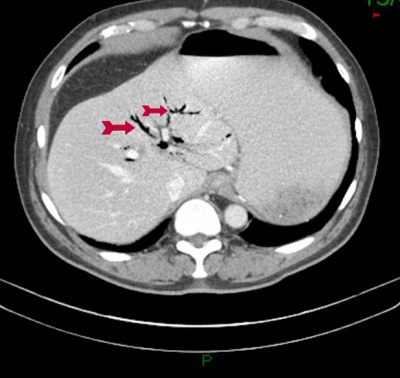

- ב- CT אפשר לראות תמונה של חסימת מעי דק עם הרחבה של לולאות מעיים ואת האבן החוסמת (תצלום 44.8)

| תצלום 44.8: חסימת מעי מאבן מרה (חץ מסמן את האבן החוסמת). | |